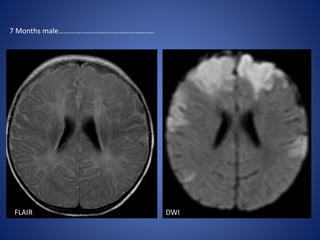

FLAIR DWI

7 Months male…………………………………………….

FLAIR DWI 7 Monthsmale…………………………………………….